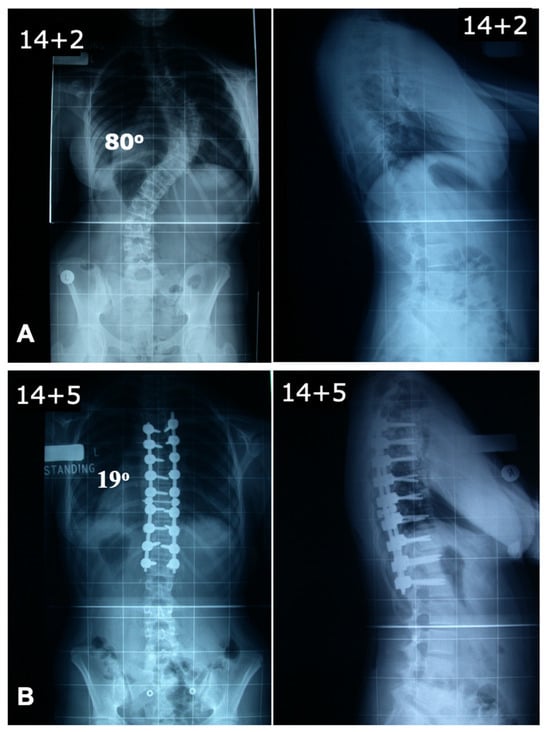

The convex pedicle screw technique in AIS, developed by Tsirikos, is a novel approach that introduced segmental correction through instrumentation and maneuvers applied on the convex side of the spinal deformity. Unlike traditional techniques focusing on concave rod engagement, this method prioritizes convex-side anchoring for improved coronal and sagittal alignment while minimizing neurological and vascular risks. The rationale for using the convex rod technique is based on several advantages, including a lower risk of neurological injury due to the reduced likelihood of medial pedicle breach (Figure 4), as well as the ability to use larger and longer pedicle screws on the convex side, which provide superior purchase and stability. Additionally, this technique facilitates improved coronal plane correction while simultaneously restoring thoracic kyphosis, which is often reduced in AIS. Another key benefit is the use of a lower implant density that reduces surgical time, blood loss, and infection risks while still achieving very satisfactory deformity correction.

The surgical procedure begins with preoperative planning using full-length standing and supine traction scoliosis radiographs complimented by a whole-spine MRI to assess curve flexibility and three-dimensional alignment. This technique can be used for any Lenke type of AIS. The patient is positioned prone on a Jackson table using a Montreal mattress to facilitate spinal alignment and a midline posterior exposure is performed, followed by subperiosteal dissection to the tips of the transverse processes. Facetectomies are routinely performed to increase segmental flexibility, which is essential for optimal correction. Pedicle screws are then placed segmentally on the convex side to allow controlled vertebral translation and coupled derotation, while only two proximal and distal screws are placed on the concave side, in order to augment the construct and provide additional stabilization.

The convex rod, which is pre-contoured to restore normal sagittal alignment, is engaged sequentially in the segmental screws. The key initial corrective maneuver involves segmental vertebral translation, where the vertebrae are gradually pulled toward the rod using reduction screws. Direct vertebral derotation is then applied at every level as the convex pedicle screws are locked into the monoaxial screws, further improving the axial deformity. A concave rod is placed once the correction is achieved and the convex rod has been secured to the spine, but its role is primarily supportive rather than corrective. The final step involves the final tightening of the screws on the rods with controlled compression and distraction at the caudal and cephalad ends in order to optimize spinal balance, followed by bone grafting using locally harvested bone and allograft, as needed, to promote fusion. A case example is shown in Figure 5.

Several studies have demonstrated the efficacy of this technique. In a comparative analysis, Tsirikos and Subramanian reported that both bilateral and unilateral screw techniques achieved satisfactory scoliosis correction; however, the unilateral [convex] approach offered reduced surgical time and blood loss, with no significant difference in clinical outcomes including patient-reported results. In addition, Tsirikos et al. applied the convex pedicle screw method across various Lenke curve types, observing significant improvements in patient-reported outcome measures [PROMs] and effective deformity correction [68]. Independent research supports these findings. Ferlic et al. compared a convex pedicle screw technique with low implant density to a traditional bilateral approach, finding comparable correction outcomes with the convex method, alongside shorter operating times and fewer implants [69]. Additionally, a study by Takahashi et al. demonstrated that convex rod rotation maneuvers, combined with direct vertebral rotation, effectively improved vertebral rotation in Lenke types 1 and 2 AIS, confirming this procedure as a viable surgical option [49].